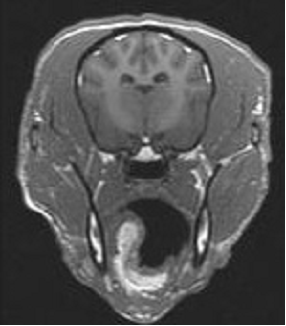

- MRI or CT to demonstrate structural changes in response to interventions

- T1, T2. PD sequences